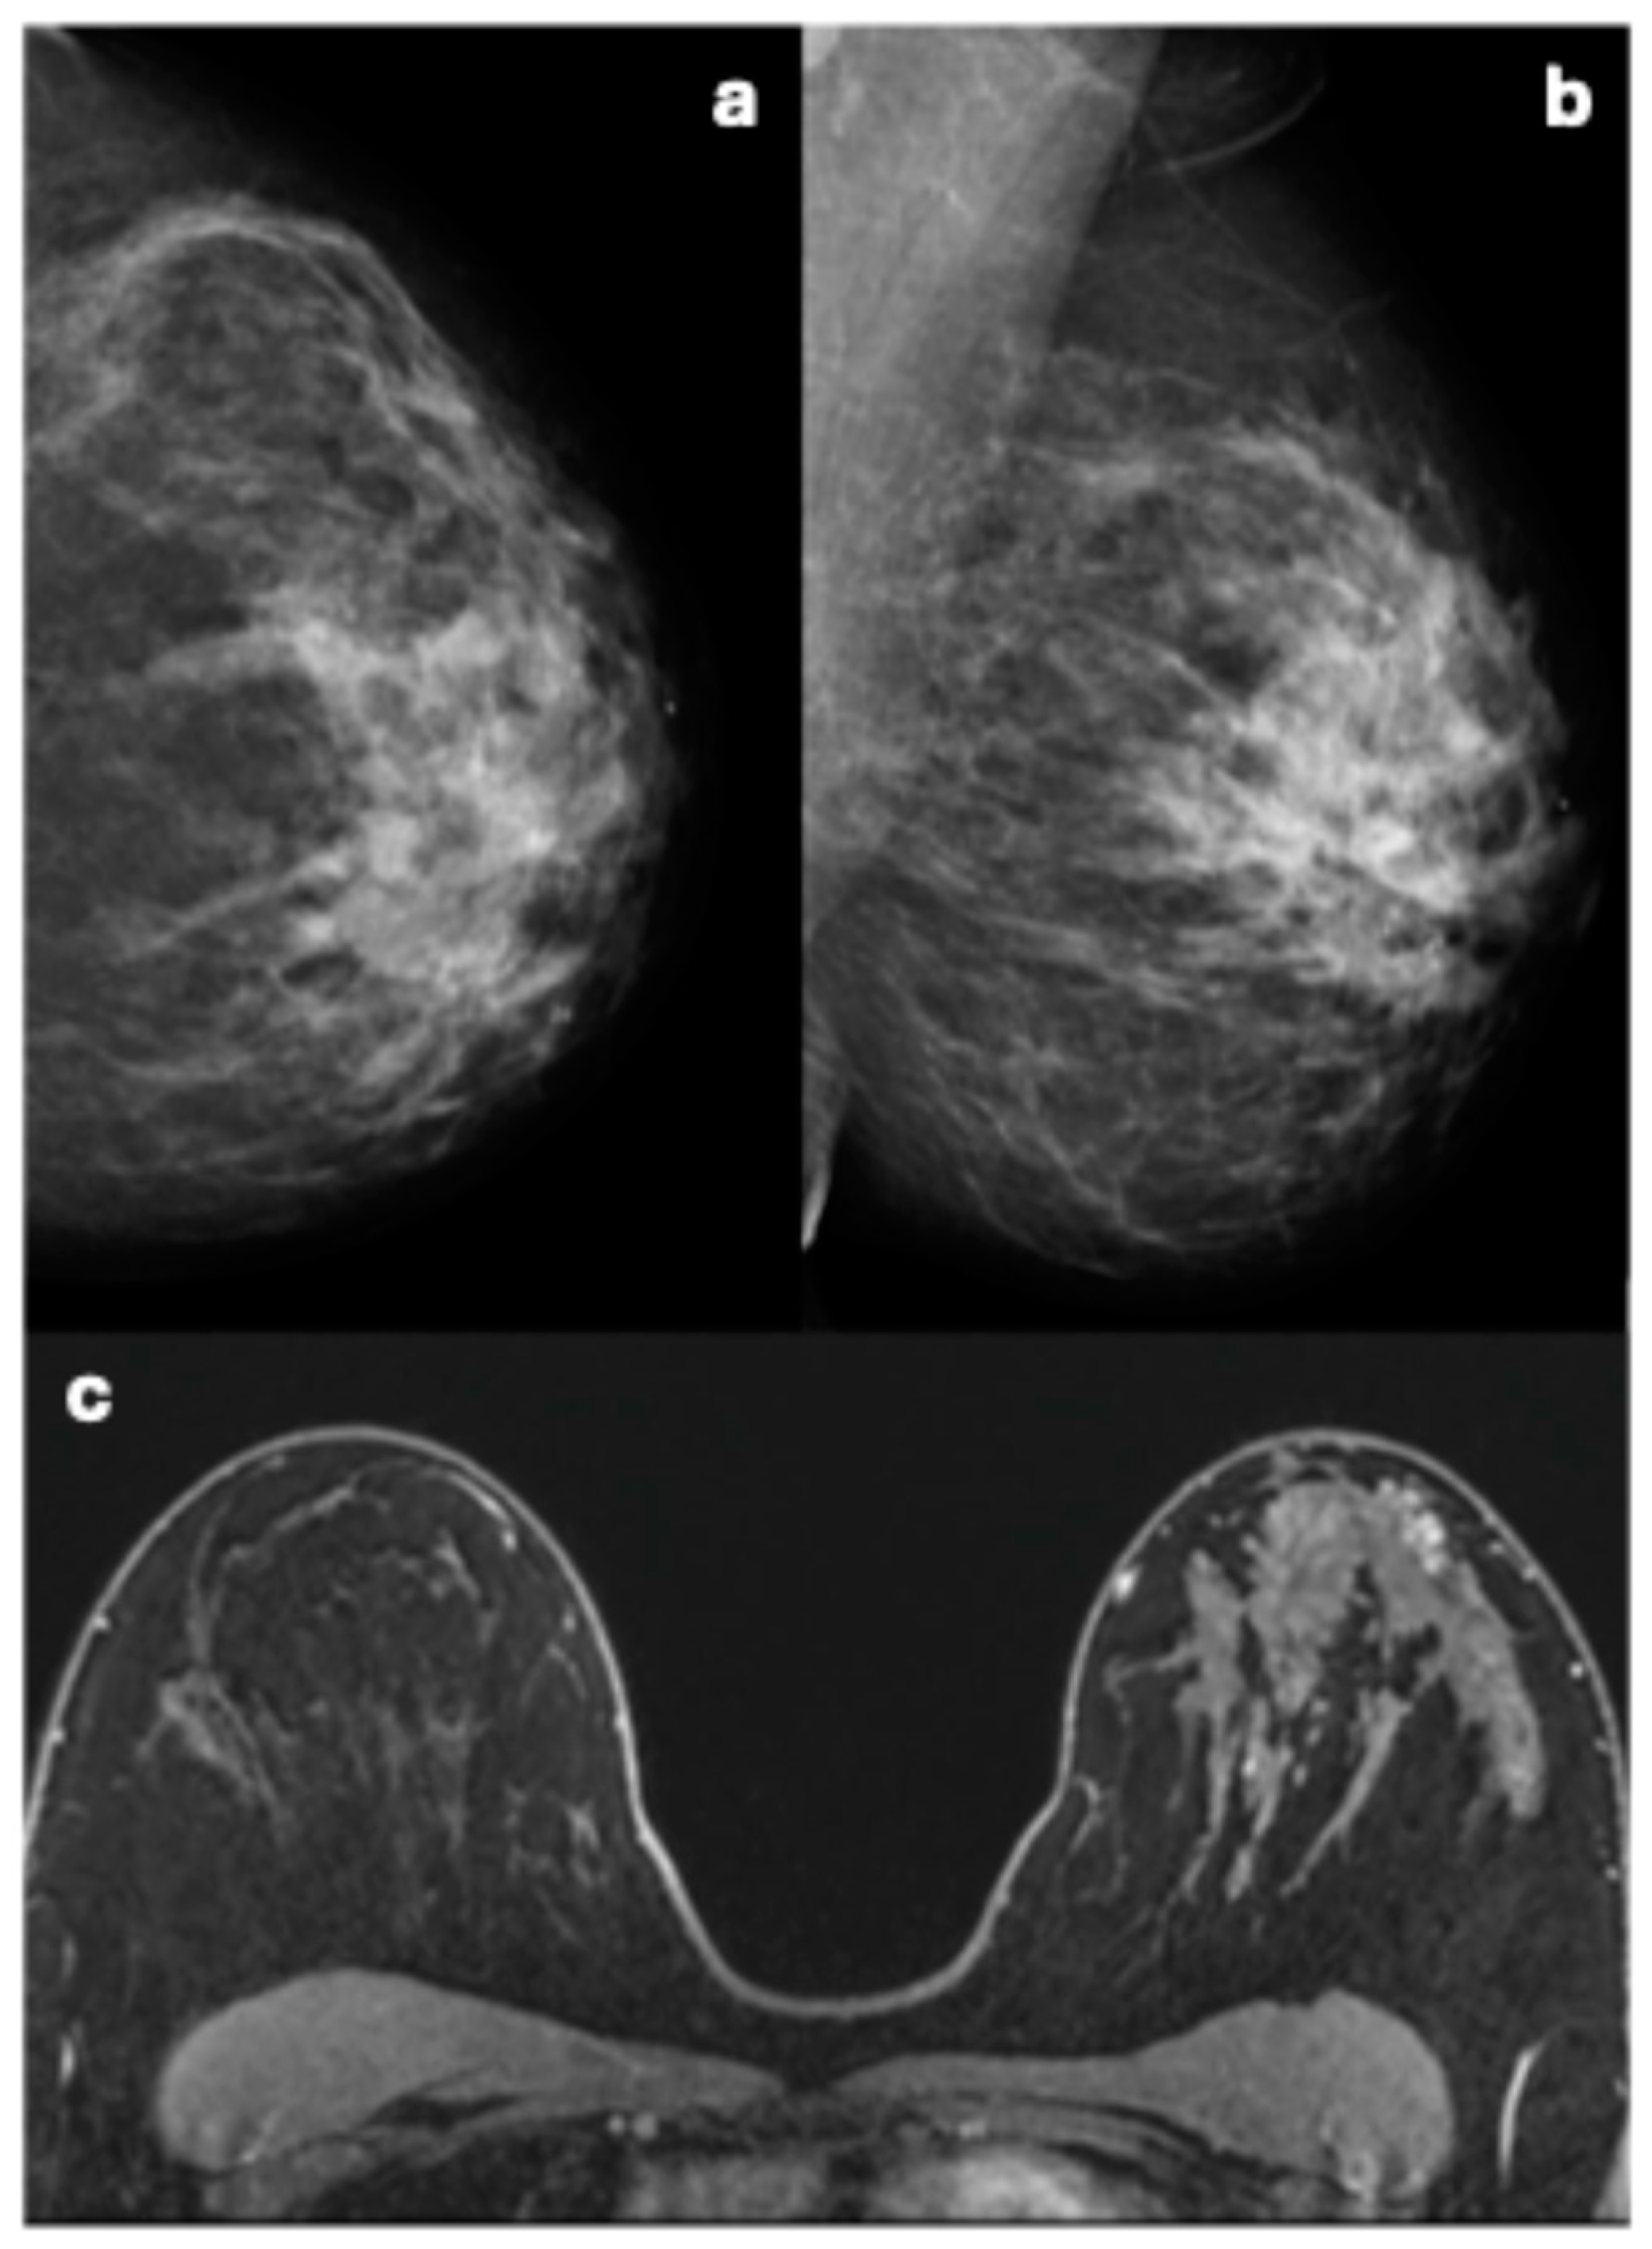

3.3. Mammographic Imaging Features and Corresponding Pathology Outcome of Breast Cancers

| Features | Breast Cancers (N = 6) Described at Mammography Re-Evaluation | |

|---|---|---|

| Breast density | A | 0 |

| B | 3 | |

| C | 2 | |

| D | 1 | |

| Lesion type | ||

| Mass | 4 | |

| Shape | Round | 1/4 |

| Irregular | 3/4 | |

| Margins | Circumscribed | 1/4 |

| Indistinct | 1/4 | |

| Spiculated | 2/4 | |

| Density | High | 4/4 |

| Asymmetry | 1 | |

| Global | 1/1 | |

| Calcifications | 1 | |

| Morphology | Fine pleiomorphic | 1/1 |

| Distribution | Regional | 1/1 |

| Associated features | 9 | |

| Nipple retraction | 1 | |

| Skin thickening | 1 | |

| Trabecular thickening | 2 | |

| Architectural distortion | 4 | |

| Type of breast cancer | NST | 4/6 |

| DCIS | 1/6 | |

| Other | 1/6 | |

| ER 1 | Positive | 3/4 |

| Negative | 1/4 | |

| PR 1 | Positive | 3/4 |

| HER2 1 | Positive | 1/4 |

| Negative | 3/4 | |

| Triple negative 1 | No | 3/4 |

| Yes | 1/4 | |

| Grade 1 | 1 | 0/4 |

| 2 | 1/4 | |

| 3 | 3/4 |